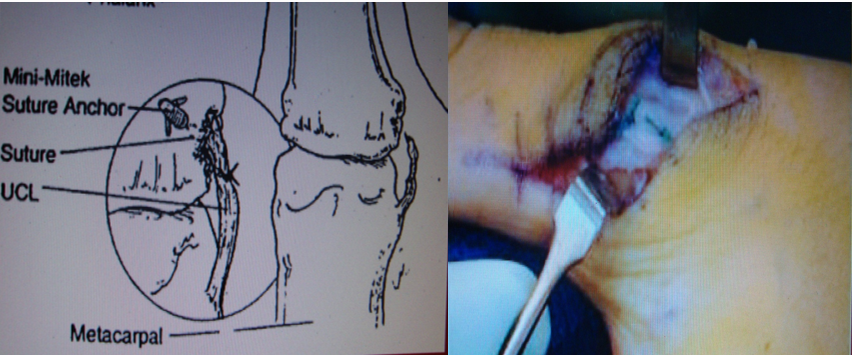

3.带线锚钉治疗侧副韧带止点断裂

传统法

带线锚钉法